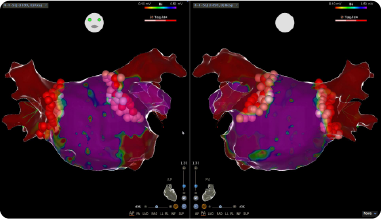

不整脈の電気生理学的マッピング画像

当院では、2018年12月からカテーテルを用いて、不整脈の出どころを焼灼して根本的に治療するカテーテル・アブレーションも開始しており、心房細動をはじめとする数種類の不整脈に対して良好な成績を上げています。